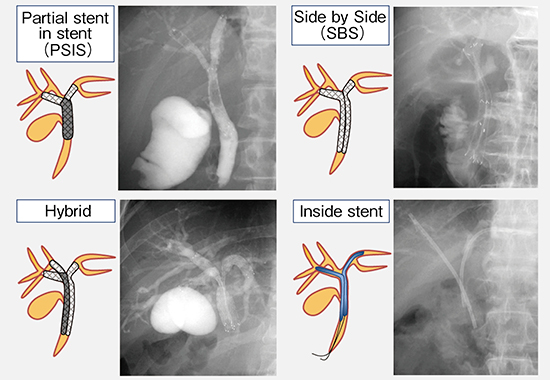

非切除肝門部胆管狭窄のドレナージ方法には、下端を重ねて留置するPartial stent in stent(PSIS)法、金属ステントを並列に2本留置するSide by Side(SBS)法、それらを組み合わせたHybrid法、プラスチックステントを胆管内に留置するInside stent法がある(図8)。

PSIS法とSBS法を比較したメタアナリシスでは、ステント開存期間はPSIS法の方がより長期に及ぶものの、手技成功率や臨床的成功率、re-interventionの割合、手技関連死亡率などは2群間で差がないことが示された6)。SBS法ではステント内腔が狭くなることが、開存期間に差が生じる要因ではないかと考えられる。

そのため、当院では通常、PSIS法を選択している。しかし、PSIS法を成功させるためには、(1) 胆管閉塞部位へのガイドワイヤの挿入、(2) 1本目のステント留置後の対側へのステントメッシュを介したガイドワイヤの挿入、(3) ステントメッシュおよび閉塞部へのデリバリーシステムの挿入という3つのハードルがある(図9)。その対策として、親水性ガイドワイヤや先端可動式カテーテルにより狭窄突破を行うほか、狭窄が強い場合は拡張用カテーテルやバルーンなどで狭窄を拡張する必要がある。また、細径デリバリーシステムの金属ステントの使用も有用である。当院での検討では、非切除悪性胆道狭窄の胆管両葉ドレナージでは、6Fr未満の細径デリバリーシステムの金属ステントを用いた場合の手技成功率が有意に高かった7)。また、傾向スコア(Propensity Score)を用いて患者背景をそろえて比較した結果、デリバリーシステム6Fr未満では6Fr以上の半分の時間でステントを留置できた。

図8 非切除肝門部胆管狭窄のドレナージ法